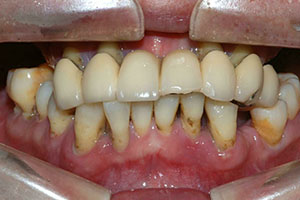

치료증례 전후사진

Before & After